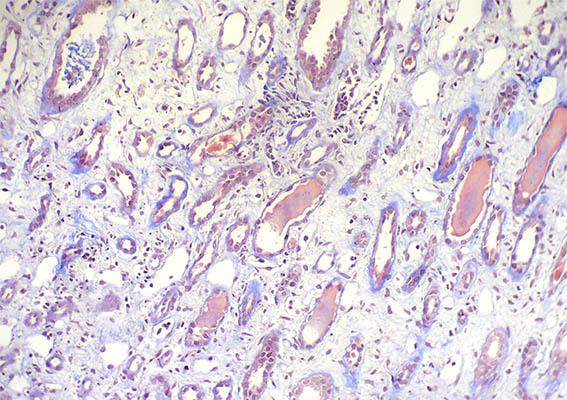

Figura 5.

H&E, X200.

Figura 6.

Tricrómico de Masson, X200.